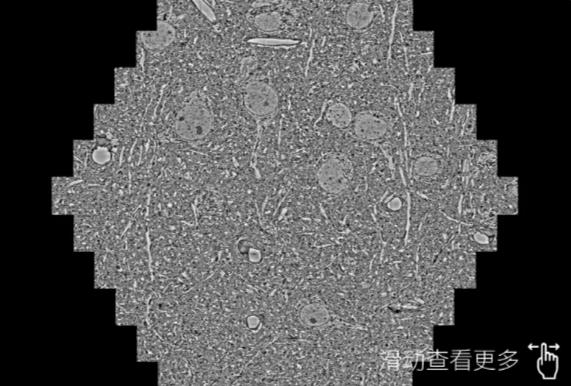

鼠脑切片。左图使用韶关蔡司韶关扫描电镜MultiSEM706对165μmx143pm面积区域成像,耗时仅需1.5秒。右图为鼠脑切片中30μm区域放大效果。样品由芝加哥大学B.Kasthuri提供。

使用蔡司高速韶关扫描电镜MultiSEM对1mm²人脑皮层组织进行高分辨成像,并对其中的各种细胞结构进行三维重构分析。左图展示了2x3mm²组织平面中锥体神经元的三维重构效果。右图显示了局部体积神经元三维重构。图像由哈佛大学chtman实验室提供,渲染图由D. Berger 制作。